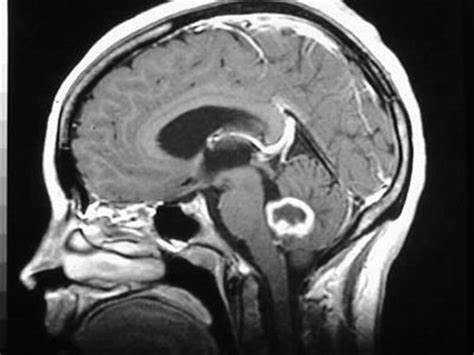

神经系统缺陷与总体预后差和寿命降低有关。但是,有许多成像方法和技术可以帮助进行术前或术中计划,以提高EOR,是对于处于挑战性位置的复杂神经胶质瘤。例如扩散张量成像,可用于描绘白质束并建立三维图以进行术前可视化。基于任务的功能性MRI(fMRI)也可用于识别与雄辩的大脑相对应的皮质和皮质下激活区域。

术中MRI(iMRI),5-氨基乙酰丙酸(5-ALA)荧光和术中超声检查等方法也可能有助于识别肿瘤边缘。尽管iMRI昂贵且可能耗时,但已证明与传统的神经导航相比,它具有更高的EOR和无进展生存期(PFS)。尽管常规的神经导航有助于肿瘤的初步定位和手术方法的优化,但准确性受横截面成像的切片厚度,跟踪方式,患者图像的配准,是手术过程中的脑移位的影响。新型的神经导航平台将能够将包括fMRI和DTI在内的多模式成像与MRI数据相结合,以进一步好转术前计划。